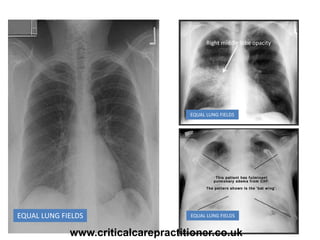

EQUAL LUNG FIELDS

Equal translucency

Air Bronchograms

Right middle lobe opacity